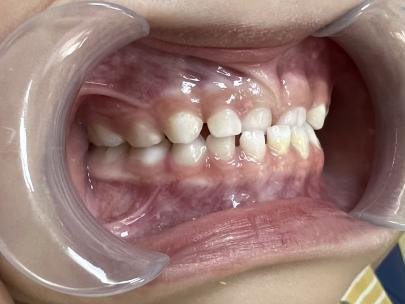

案例一:

治疗前